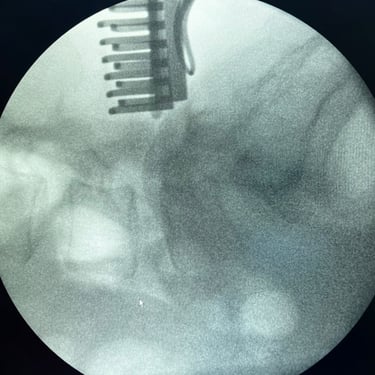

Cirugía de Hernia Lumbar | Discectomía Lumbar

La hernia lumbar ocurre cuando parte del disco intervertebral se desplaza y comprime las raíces nerviosas, generando dolor lumbar, ciática y debilidad en las piernas. Cuando el tratamiento médico no alivia los síntomas, la opción más efectiva es la discectomía lumbar, una cirugía destinada a retirar el fragmento herniado del disco que presiona el nervio. Este procedimiento, realizado mediante técnicas microquirúrgicas, busca aliviar el dolor y recuperar la función neurológica. La recuperación suele ser rápida, permitiendo al paciente reincorporarse gradualmente a sus actividades. La cirugía ofrece altas tasas de éxito y mejora significativa de la calidad de vida.